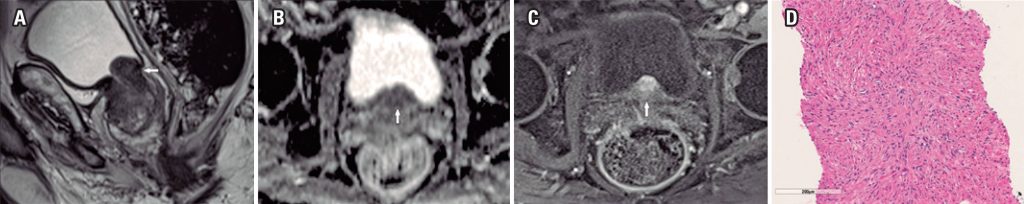

Achados de imagem na ressonância magnética multiparamétrica dos leiomiomas prostáticos puros

Encontramos três casos confirmados histologicamente de leiomiomas prostáticos puros (0,02%) em nossa casuística e descrevemos os achados da ressonância magnética multiparamétrica destes casos de leiomiomas. Os achados de imagem foram semelhantes aos de lesões com moderada ou alta suspeição para neoplasia clinicamente significante (Likert 4 ou 5) quando localizados na zona de transição ou zona periférica da próstata.

Leiomiomas puros da próstata tiveram achados de imagem na ressonância magnética multiparamétrica que mimetizaram adenocarcinomas. Radiologistas, urologistas e patologistas devem estar cientes destas entidades e seus achados de imagem.